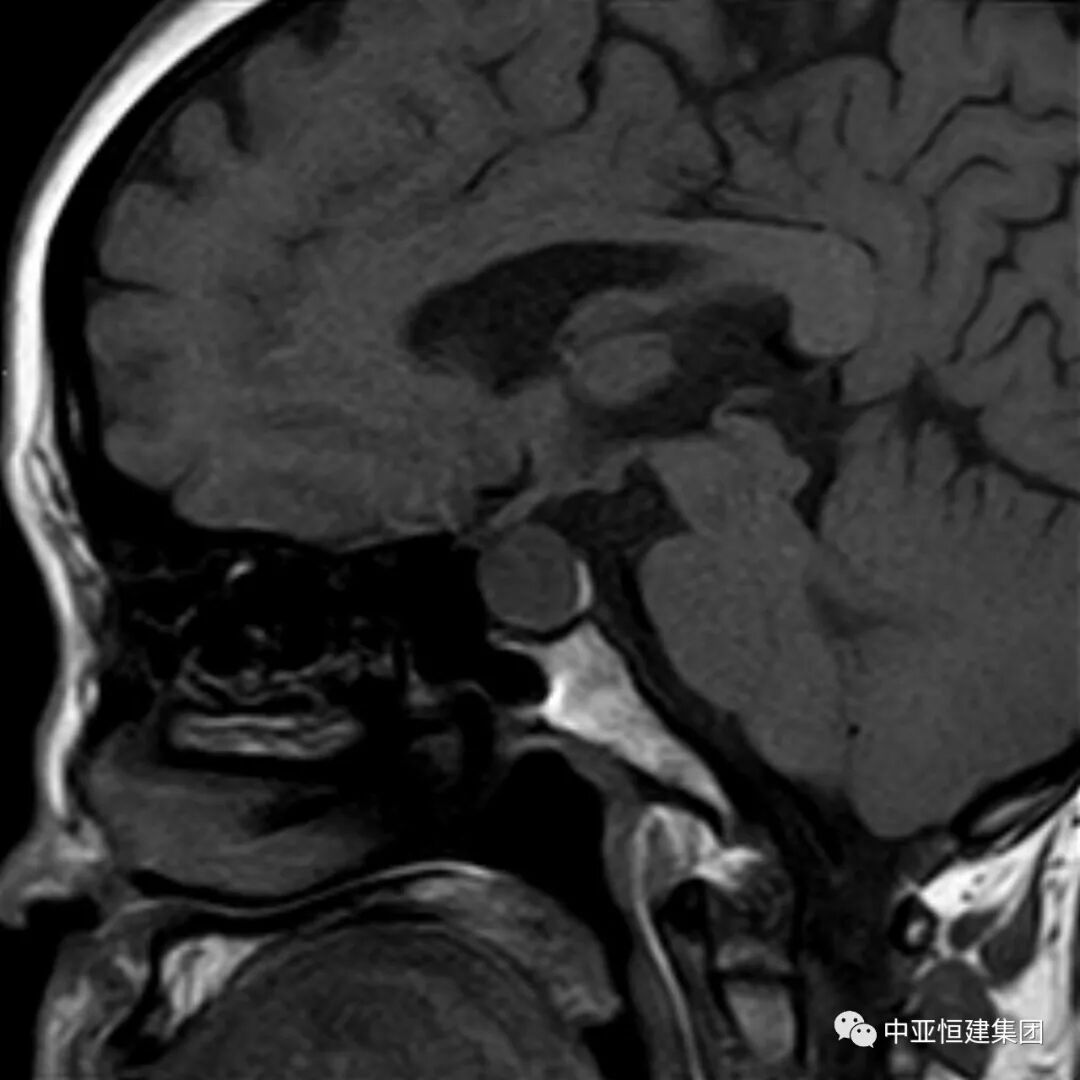

患者做头CT时未见明显异常

同一患者患者做MRI发现垂体瘤

MRI增强目前是垂体瘤诊断主要检查方式之一,垂体微腺瘤一般用冠状面和矢状面薄层,包括 T1 和 T2 图像。

T1 微腺瘤呈低信号,多位于垂体一侧,T2微腺瘤呈高信号或等信号。动态增强扫描,肿瘤信号早期低于垂体,后期高于垂体。